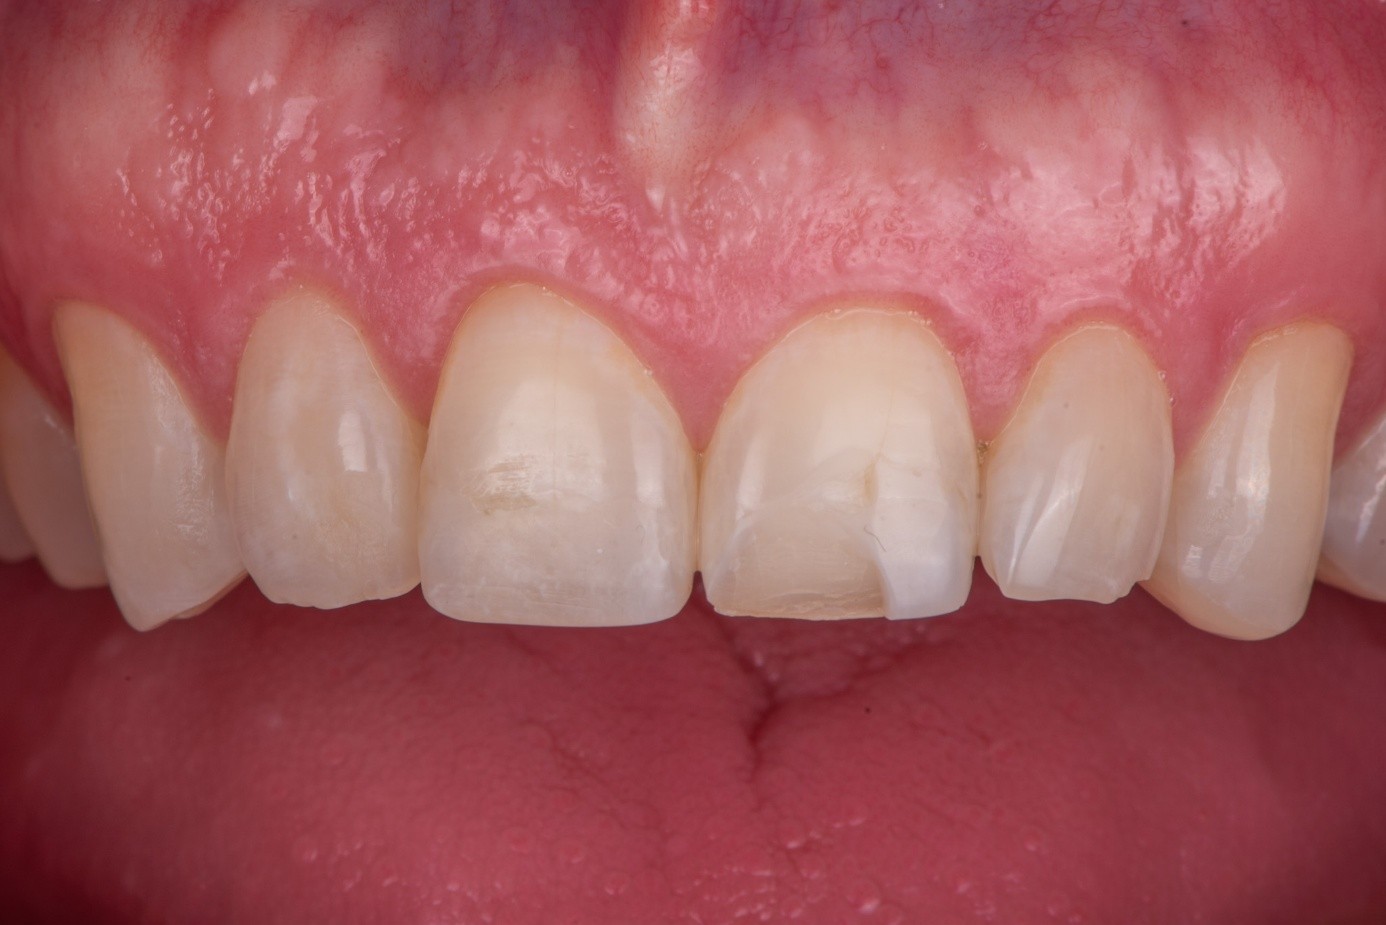

This case involved a patient with multiple feldspathic porcelain restorations done more than 15 years ago in the esthetic zone. Multiple restorations presented with tissue recession and marginal discoloration, some also presented with microcracks that were visible during clinical examination and were in need of replacement in the near future. However, the patient was not financially committed to replace the other failing restorations. Maxillary right lateral incisor presented with an unusual failure pattern: The incisal third remained fully bonded and intact, while the middle-to-cervical portion of the veneer was fractured away as a single piece (Figure 2). This type of fracture could be described as a cervical shear fracture with incisal retention—a form of mixed failure, since part of the restoration remained bonded but the majority separated cleanly. Examination revealed almost no adhesive layer on the tooth surface, while the fractured restoration still showed adhesive remnants (Figure 3). This indicated that the weak point was the interface between adhesive and tooth substrate, rather than between ceramic and adhesive.

(2.) An intraoral view of the maxillary anterior region, where most teeth are restored with ceramic facings. The upper lateral incisor is fractured, with only the ceramic in the incisal third remaining in place. The cervical and middle thirds of the facing are lost, exposing the underlying tooth structure.

Figure 2